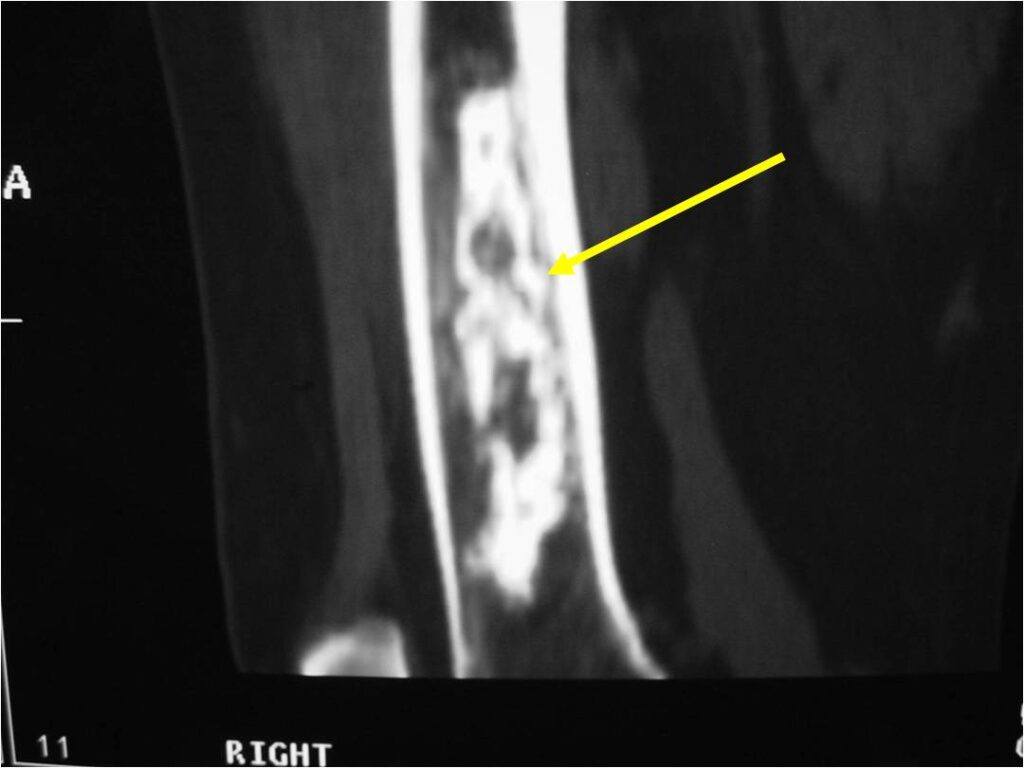

- Localized, radiolucent defect usually with punctate calcifications

- Calcifications are stippled, punctate, popcorn like calcifications and “Ring and Arc” calcifications

- Cartilage tumors grow in a lobular manner. The perimeters of the lobules undergo

- enchondral ossification that may calcify. If the entire perimeter of the lobule calcifies it appears

- radiographically as a “Ring”. If a portion of the perimeter of a lobule calcifies it forms an “Arc” on

- an X-ray.

Plain X-Ray:

- Geographic lytic lesion

- Central often metaphyseal in long bones

- Chondroid matrix with calcifications in majority of tumors